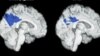

خواب ضایعات مغز را دفع می کند

هنگامی که ما درخواب هستیم، مغزمان علاوه بر نیروگیری و آماده سازی خود برای روز بعد، سرگرم انجام اموردیگری هم میشود.

مغز انسان ظاهراً مشغول گونه ای تمیزکاری هم میشود که دانشمندان را امیدوار ساخته، به درمان بیماری هایی نظیر آلزایمر بیانجامد.

خواب می تواندسمومی را دفع کند که در طول روز در مغز جمع می شوند.

به گفتۀ پژوهشگران، مطالعه همچنین آشکار ساخته که نحوۀ منحصر به فرد دفع به اصطلاح زباله ها از مغز در طول مدت خواب، به شدت فعال می ماند و سموم بیماری آلزایمرآور و حتی سایر اختلالات و بی نظمی های عصبی را می زداید.

ضمناً، پژوهش گران این را هم دریافته اند که حین خواب، سلول های مغز کوچک تر میشوند و عمل تمیزکاری در اطراف آنها آسان تر و مؤثرتر صورت می گیرد.